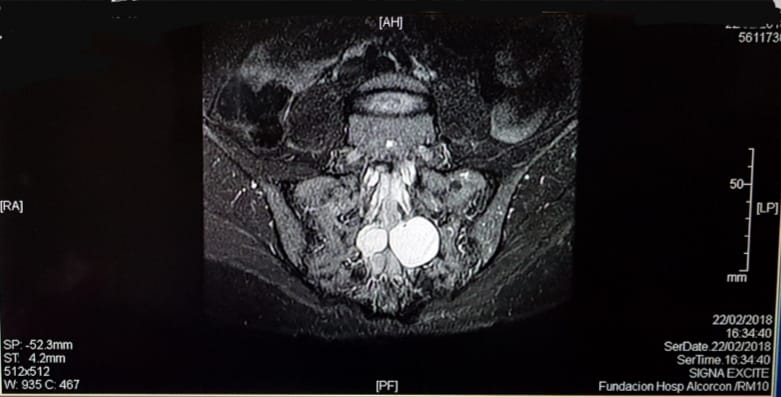

Los quistes de Tarlov son dilataciones aracnoideas de la médula espinal ocupadas por líquido cefalorraquídeo que se pueden dar a cualquier nivel de la columna vertebral, aunque lo más frecuente es que aparezcan en la parte inferior, llamada región sacra. A pesar de que es habitual su presencia en la población general, se estima que sólo un 5% de los pacientes presentan síntomas.